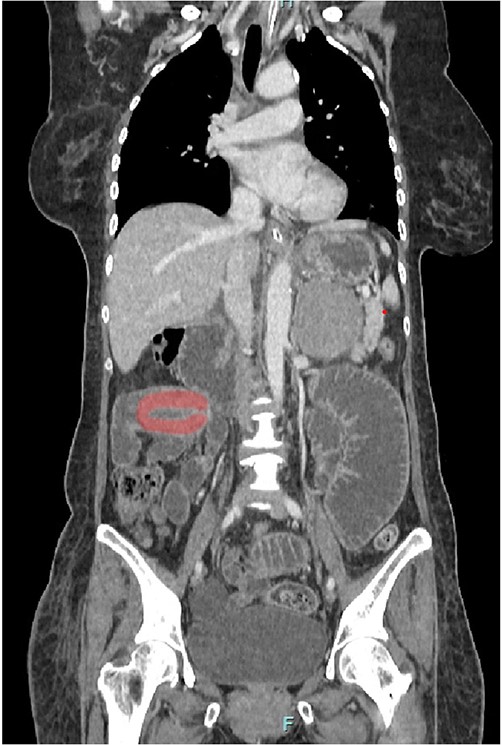

Her abdominal x-ray showed a dilated small bowel with a most likely transition point at the ileum and a collapsed large bowel (Fig. 1). Computed tomography (CT) of the abdomen showed an intussusception with the transition point at the proximal ileum with mesenteric invagination (Figs. 2 and 3).

Coronal view of CT scan. Intussusception transition point is seen likely at the proximal ileum with evidence of ‘bowel in bowel’ appearance, measuring ~7.8 cm.